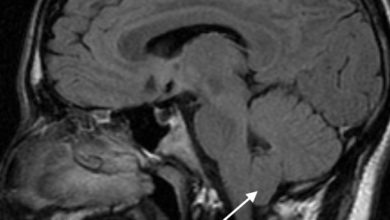

Chiari tip1 malformasyonu

Primer serebellar ektopi olarak da adlandırılır. Serebellar tonsiller foramen magnum düzeyinden 3mm’ den daha fazla üst servikal spinal kanala herniye…